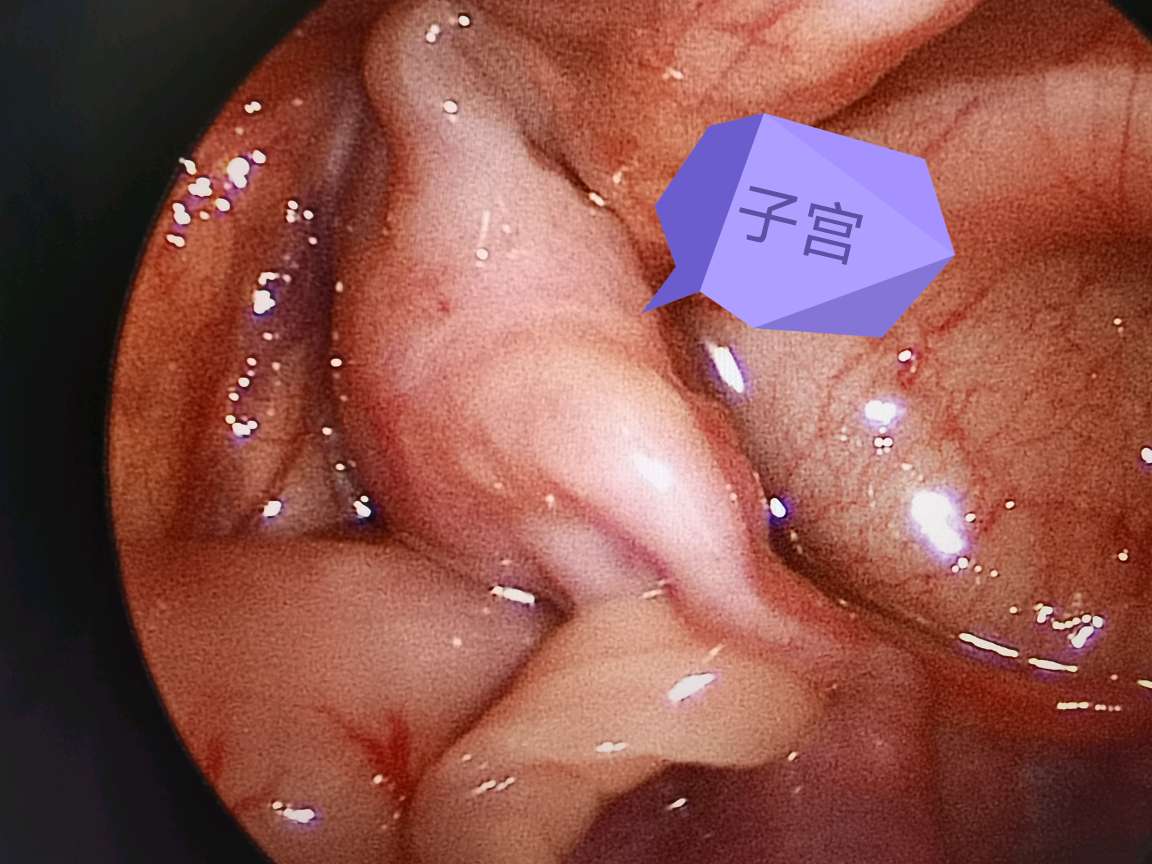

卵巢及子宫嵌顿

鞘突管未闭